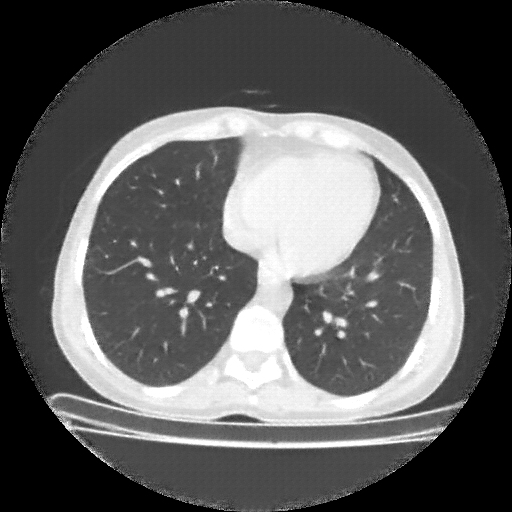

Original VENOUS CT scan

Full window (WL 1023.5, WW 4095 β†’ Low βˆ’1024, High +3071)

Lung window (WL -600, WW 1500 β†’ Low βˆ’1350, High +150)

Mediastinum window (WL 40, WW 400 β†’ Low βˆ’160, High +240)